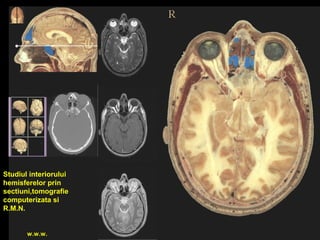

Studiul interiorului

hemisferelor prin

sectiuni,tomografie

computerizata si

R.M.N.